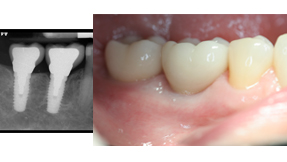

Posterior Implants (Back teeth)

The vast majority of posterior implants are predominantly facilitating function and health. The placement of back teeth is essential because of the majority of the chewing function is on the back teeth. The major benefits include preseveration of the jaw bone, preservation of adjacent teeth structure and eliminating the need for a bridge and prevention of facial collapse which prevents premature aging. Premature aging is prevented by maintaining esthetic dimensions of the dental facial spatial complex, the vertical dimension from the tip of your nose to your chin (occlusion)- bite. The loss of teeth accentuates this, and thus deepens the folds in your face.